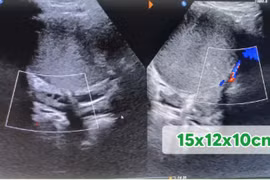

​Kết quả thăm khám và siêu âm cho thấy tử cung to hơn bình thường, đường kính trước – sau 52 mm, độ dày nội mạc tử cung 9 mm. Tại thành trước tử cung xuất hiện khối u có cấu trúc khác mô cơ, kích thước khoảng 76 × 65 × 73 mm, có tín hiệu mạch rải rác. Ngoài ra, tại thành sau đoạn eo tử cung cũng ghi nhận một khối u tương tự, kích thước 21 × 24 mm.